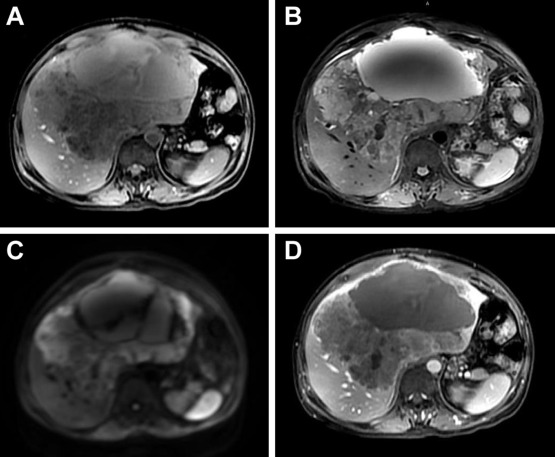

A 52-year-old man presented with abdominal fullness and pain and body weight loss of 5 kg in the past 6 months. He had a history of nonkeratinizing undifferentiated NPC, cT2aN2M0, Stage III and underwent concurrent chemoradiotherapy 4 years ago. There was no evidence of local recurrence in his recent regular follow-up examinations. He also had history of gastric ulcer bleeding and received subtotal gastrectomy 25 years ago. He had no known specific family history. He drank alcohol occasionally and was also a smoker for 25 years. Physical examinations revealed hepatomegaly (liver span of 15 cm in the right subclavian line and 9 cm in the sternum midline) with local tenderness over the epigastric region. Laboratory data showed anemia with hemoglobin 9.8 mg/dL (normal range: 13–17 mg/dL); normal serum total bilirubin 0.4 g/L (normal range: 0.5–1.5 g/L); normal aspartate aminotransferase 27 U/L (normal range: < 37 U/L); normal alanine aminotransferase 15 U/L (normal range: < 40 U/L); abnormal serum alkaline phosphatase 489 U/L (normal range: 40–129 U/L); abnormal r-glutamyl transpeptidase 302 U/L (normal range: 5–36 U/L); normal serum α-fetoprotein 2.05 ng/mL (normal range: < 5.0 ng/mL); normal carcinoembryonic antigen 2.83 ng/mL (normal range: < 5.0 ng/mL); abnormal serum carbohydrate antigen 19-9 53.4 ng/mL (normal range: 0–37 ng/mL); and abnormal anti-squamous cell carcinoma antigen 8.1 ng/mL (normal range: 0–2.1 ng/mL). Hepatitis B surface antigen and hepatitis C virus antibody were both negative. Blood EBV viral load was 82,801 copies/mL. Stool examination was normal. Abdominal plain film radiography disclosed no remarkable findings, except a nonspecific bowel gas pattern. Abdominal ultrasonography showed a lobulated cystic lesion about 20 cm × 16.5 cm × 17 cm, with mixed solid and cystic parts occupying occupying both lobes of the liver. Abdominal magnetic resonance imaging (MRI) showed a well-defined, lobulated cystic lesion with poor contrast enhancement occupying both lobes of the liver (Fig. 1). Nasopharyngoscopy performed by an ear, nose, and throat specialist demonstrated no local mass lesions. Only mild protruding on the central part of nasopharynx was noted and biopsies were taken. Esophagogastroduodenoscopy was performed to exclude malignancy of upper gastrointestinal origin. Only esophageal Candida colonization was found. For the definite diagnosis, biopsies from this cystic lesion were performed with the assistance of ultrasonography.

A large, well-defined, lobulated mixed cystic and solid lesion occupying both ...

Figure 1.

A large, well-defined, lobulated mixed cystic and solid lesion occupying both lobes of the liver showed hypointensity on T1-weighted imaging (A), hyperintensity on T2-weighted imaging (B), and diffusion-weighted imaging (C). During dynamic study, the lesion revealed poor contrast enhancement (D).